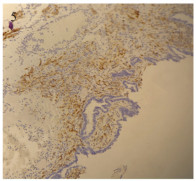

Competing interests: The authors declare that they have no competing interests.作者贡献:王立娟: 论文撰写邹凌凤: 提供病例郭小红: 论文指导曹晓静: 图片制作王军大: 提供影像学图片曾敏: 文章审校 -